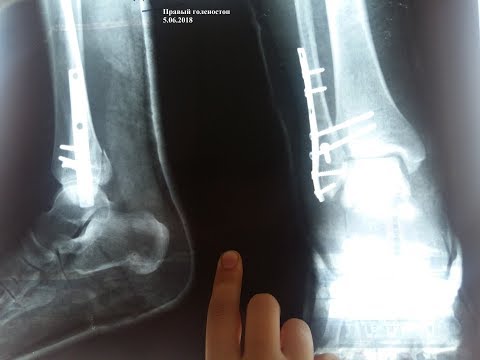

- Фиксация отломков кости при помощи различных приспособлений, например, гвоздя. После операции пациента обездвиживают на 3 недели. Нагружать больную ногу запрещается около полугода.